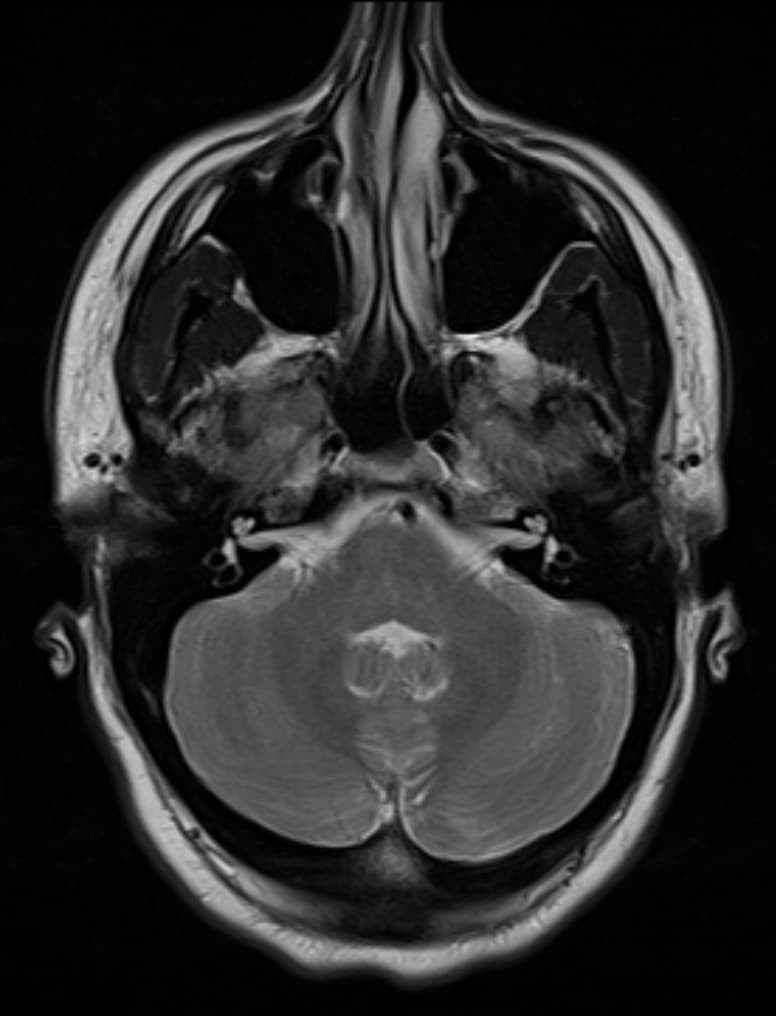

Nasal septum deviation is a physical disorder of the nose, involving a displacement of the nasal septum. Some displacement is common, affecting 80% of people, mostly without their knowledge. The nasal septum is the bone and cartilage in the nose that separates the nasal cavity into the two nostrils. The cartilage is called the quadrangular cartilage and the bones comprising the septum include the maxillary crest, vomer, and the perpendicular plate of the ethmoid. Normally, the septum lies centrally, and thus the nasal passages are symmetrical. A deviated septum is an abnormal condition in which the top of the cartilaginous ridge leans to the left or the right, causing obstruction of the affected nasal passage. It is common for nasal septa to depart from the exact centerline; the septum is only considered deviated if the shift is substantial or causes problems. By itself, a deviated septum can go undetected for years and thus be without any need for correction. Symptoms of a deviated septum include infections of the sinus and sleep apnea, snoring, repetitive sneezing, facial pain, nosebleeds, mouth breathing, difficulty with breathing and mild to severe loss of the ability to smell. Only more severe cases of a deviated septum will cause symptoms of difficulty breathing and require treatment. It is most frequently caused by impact trauma, such as by a blow to the face. It can also be a congenital disorder, caused by compression of the nose during childbirth. Deviated septum is associated with genetic connective tissue disorders such as Marfan syndrome, homocystinuria and Ehlers–Danlos syndrome. Nasal septum deviation is the most common cause of nasal obstruction. A history of trauma to the nose is often present including trauma from the process of birth or microfractures. A medical professional, such as an otorhinolaryngologist (ears, nose, and throat doctor), typically makes the diagnosis after taking a thorough history from the affected person and performing a physical examination.